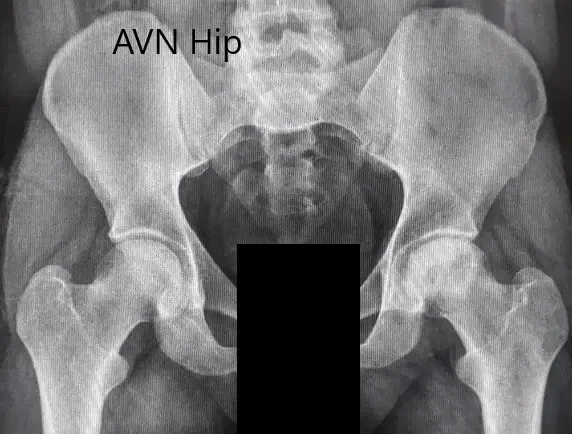

Imaging studies obtained in the form of an X-Ray suggested sclerosis of the left head of the femur. There were marked acetabulum changes. An MRI was further obtained suggesting avascular necrosis of the superior lateral head of the femur with changes in the acetabulum. There was marked hypointense areas on both T1WI and T2WIs.

Preoperative X-ray of the pelvis with both hips in anteroposterior view showing AVN of the Left Hip.

Preoperative X-ray of the pelvis with both hips in the frog-legged lateral view showing AVN of the Left Hip.